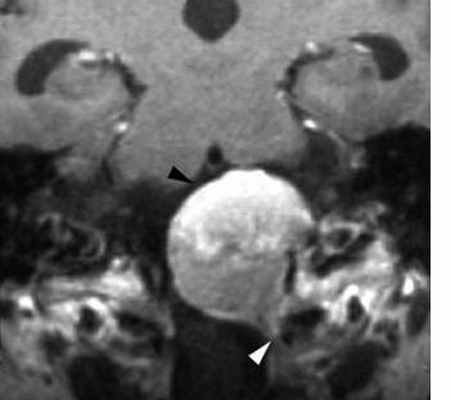

Менингиома может развиться из любого участка стенки задней черепной ямки, но чаще из свободного края намета мозжечка и в области большого затылочного отверстия. Эти менингиомы при МРТ головного мозга имеют те же черты, что и характерные для супратенториальных менингиом. Дополнение стандартной МРТ МР-венографией помогает выявить компрессию поперечного синуса.

МРТ головного мозга. Менингиома задней черепной ямки. Аксиальная Т1-зависимая МРТ с контрастированием.

МРТ головного мозга. Менингиома области большого затылочного отверстия с компрессией ствола мозга. Корональная Т1-зависимая МРТ с контрастированием.